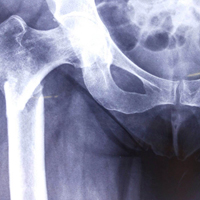

Case:1 Polytrauma Case (Multiple Fractures in Ipsilateral Limb)

Pre-Op Hip (AP & Lateral)